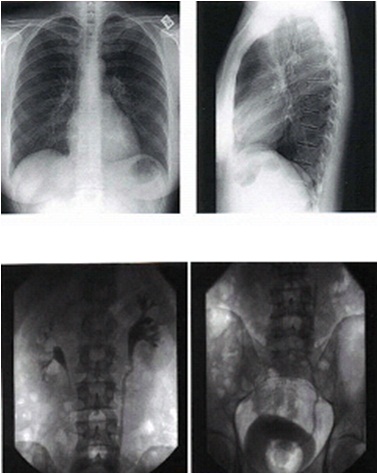

![]() | ||

| Contoh gambar organ dalam ketika difoto dengan sinar-X |